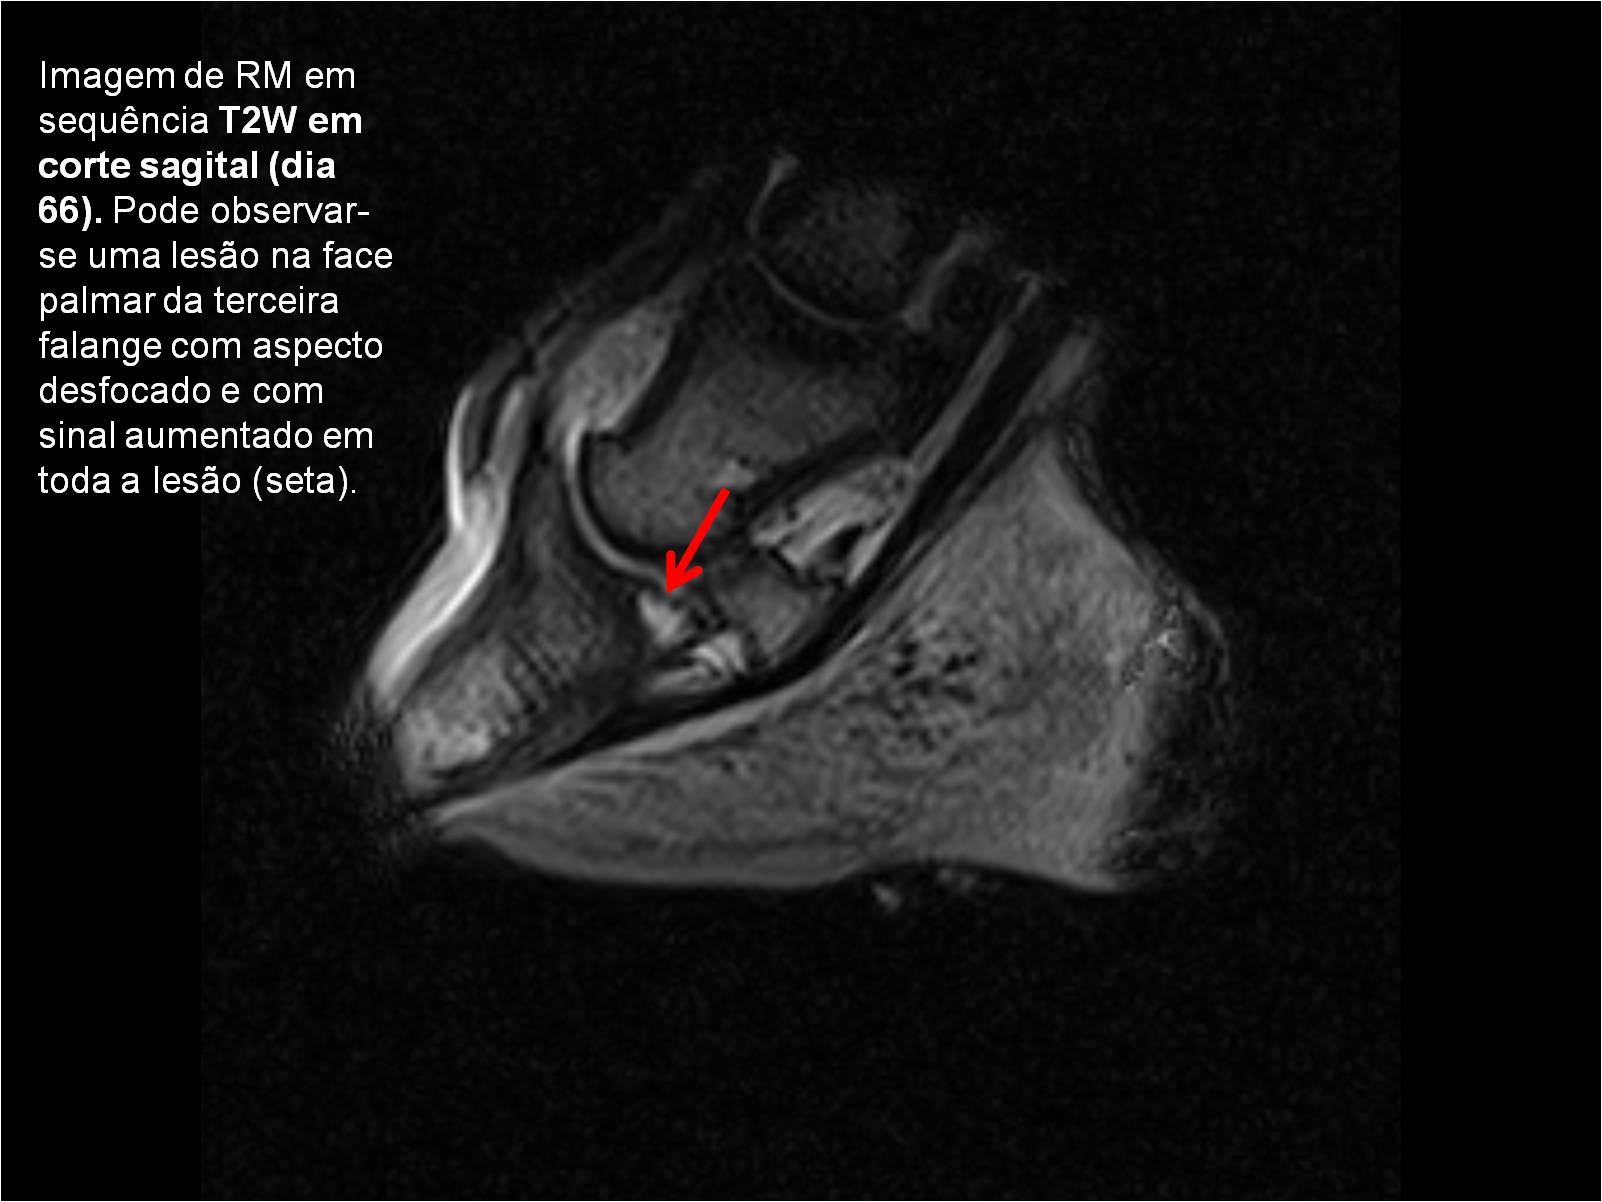

Publisher: Universidade de Évora

Abstract: O relatório de estágio encontra-se estruturado em três partes distintas. A primeira parte faz a caracterização das infraestruturas e funcionamento do Hospital Veterinário de Equinos de Lüsche, Oldenburg, Alemanha, assim como a análise casuística dos casos clínicos acompanhados durante os 6 meses de estágio. A segunda parte consiste de uma revisão bibliográfica sobre quistos do osso subcondral em equinos. Por fim, a terceira parte consta da apresentação e discussão de um caso clínico, nomeadamente o diagnóstico e acompanhamento imagiológico, por ressonância magnética, de um quisto subcondral na terceira falange num cavalo adulto; ### Abstract Equine Practice- Subcondral bone cyst of the third phalanx This internship report is divided in three parts. The first part characterizes the infrastructure and function of the Equine Hospital Lüsche, Oldenburg, Germany, as well as the casuistic of the clinical cases accompanied during the 6 month internship. The second part consists in a bibliographic review of cystic lesions of the subchondral bone in equines. The third part consists in a case report, the diagnostic and imagiological accompaniment, by use of magnetic resonance imaging, of a subchondral bone cyst in the distal phalanx of an adult equine.